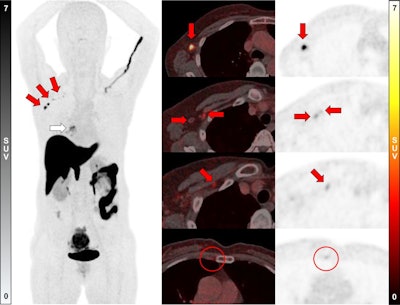

A 58-year-old woman was diagnosed with ER-positive (Allred score 8) ILC in her right breast. Ultrasound and MRI found prominent lymph nodes in right axillary level I area, diagnosed as metastasis on ultrasound-guided fine-needle aspiration. F-18 FES-PET/CT showed a positive mass in right breast (white arrow; SUVmax, 5.6) and multiple F-18 FES–positive lymph nodes in right axillary level I, II, and II/III junction areas (red arrows; SUVmax, up to 12.2). In addition, a small F-18 FES-positive lymph node was observed in the right second internal mammary area (red circles; SUVmax, 1.8). However, biopsy could not be performed because it was too small and not visible on ultrasound; the clinician decided to include internal mammary lymph node in treatment field for adjuvant radiotherapy. The patient underwent lumpectomy with ALN dissection, with five metastases being identified in 13 lymph nodes dissected, and is scheduled to receive adjuvant chemotherapy, radiotherapy, and endocrine therapy.Journal of Nuclear Medicine